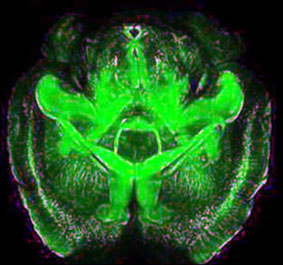

Bước tiến mới trong khám phá bí ẩn não bộ

Người đi tìm những “mảnh ghép” còn thiếu trong hành trình giải mã bệnh hiếm